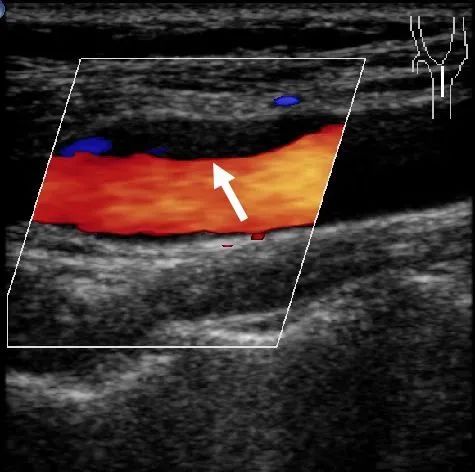

颈动脉斑块 超声示意图

颈动脉超声是诊断和评价颈动脉壁疾病的有效方法之一。检查的目的是判断有无血管壁增厚,硬化或狭窄等。正常颈动脉血管内中膜无增厚、无斑块形成,血管不狭窄,无闭塞。

颈动脉彩超不仅能清晰显示血管内中膜增厚、有无斑块形成、斑块形成的部位、大小、是否有血管狭窄及狭窄程度、有无闭塞等详细情况,并能进行准确的测量及定位,还能对检测动脉血流速度及阻力进行测量。特别是可检测早期颈动脉粥样硬化病变的存在,使患者得到及时预防。